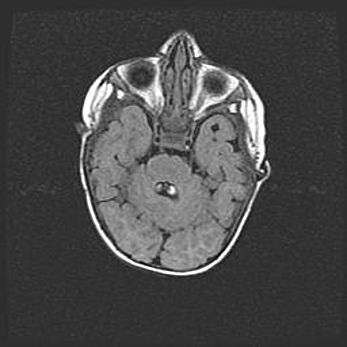

Множественные кисты обоих полушарий головного мозга, наибольшая из них в правой затылочной области. Ассиметричная атрофическая гидроцефалия.

Возраст: 7 месяцев

Вес: 5660 г

Пол: мужской

Окружность головы: 41,5 см

Срок гестации: 28-29 недель

Кисты головного мозга развиваются в результате многоочаговых некрозов вещества мозга и возникают вследствие перенесенной перинатальной инфекции, менингитов, энцефалитов, асфиксии, родовой травмы, расстройств мозгового кровообращения различного генеза. Образованию кист в веществе головного мозга плодов и новорожденных способствуют такие факторы, как высокое содержание в нем воды, недостаточная (или отсутствие) миелинизация и слабая астроглиальная реакция на повреждение.

Кисты могут сочетаться с гидроцефалией и другими поражениями головного мозга.